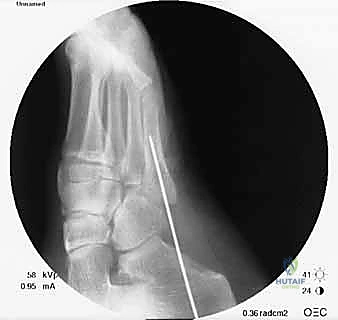

- يتم تجهيز غرفة العمليات بأحدث أجهزة التصوير الإشعاعي الفوري (C-arm) لضمان الدقة المطلقة.

- إدخال سلك التوجيه (Guide Wire): تحت توجيه الأشعة السينية المباشرة في غرفة العمليات، يتم إدخال سلك معدني رفيع جداً ليمر عبر الكسر وصولاً إلى النخاع العظمي. هذه الخطوة تتطلب دقة متناهية لضمان أن السلك في المنتصف تماماً.

- التحضير والتوسيع (Drilling/Tapping): يتم استخدام مثقاب خاص مجوف يمر فوق سلك التوجيه لتوسيع القناة النخاعية وتجهيزها لاستقبال المسمار.

- إدخال المسمار التيتانيوم (Screw Insertion): يتم اختيار مسمار طبي من التيتانيوم (طوله وسمكه محسوبان بدقة لتناسب عظمة المريض). يتم إدخال المسمار ليربط بين جزئي الكسر، مما يولد قوة ضغط (Compression) تجعل حواف العظم متلاصقة تماماً، وهو السر وراء الالتئام السريع.